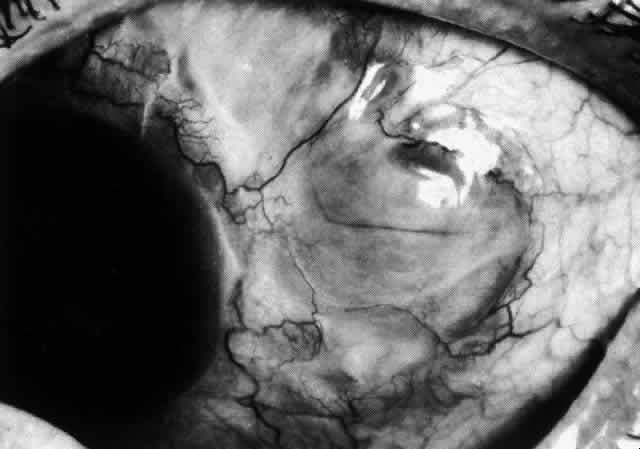

The characteristic features of necrotizing scleritis on fluorescein angiography are hypoperfusion and, eventually, nonperfusion of the vascular networks (Figs. 40 through 43).26 The initial changes are on the venous side of the capillary network; the transit time of the dye increases even if the eye is red and congested. If the disease process persists or has been present for a long time, thrombosis and permanent vaso-occlusive changes occur. These vessels (or the occluded capillary network) are bypassed by the opening of anastomotic channels. New vessels in a granuloma give rise to deep intrascleral leakage of dye (see Fig. 43). Conjunctival and episcleral involvement by the destructive change is late but is always preceded by vaso-occlusive changes that can sometimes be detected with use of the red-free light on the slit lamp (Figs. 44 and 45).

Fig. 40. Early necrotizing scleritis. There is characteristic yellow discoloration of the sclera underlying the conjunctiva at a point of necrosis. In this instance a small filament of tissue has penetrated the conjunctiva.

Fig. 41. Late stage of fluorescein angiogram adjacent to the site of necrosis in the same patient as in Figure 40. Although the eye is uniformly congested, the area near the necrosis shows vascular shutdown, whereas the rest of the conjunctiva and episclera is normally perfused.

Fig. 42. Late arterial phase of fluorescein angiogram in a patient with necrotizing scleritis. All the vessels except the main trunk and the vessels around the limbal perforating vessels are occluded and remain unperfused throughout the angiogram.

Fig. 43. Late venous phase of angiogram of a patient with necrotizing scleritis showing late deep leakage from vessels on the surface of the sclera and leakage of the capillary network at the limbus and the vessels draining it, together with poor or absent perfusion of the remaining vessels.

Fig. 44. Necrotizing scleritis. An avascular patch is seen in red-free light. If left untreated, this will progress to the situation found in Figure 45.

Fig. 45. Necrotizing scleritis. An area of necrosis is evident in the eye of this patient with localized Wegener's granulomatosis. The conjunctiva adjacent to the white necrotic tissue becomes adherent to the underlying episclera.